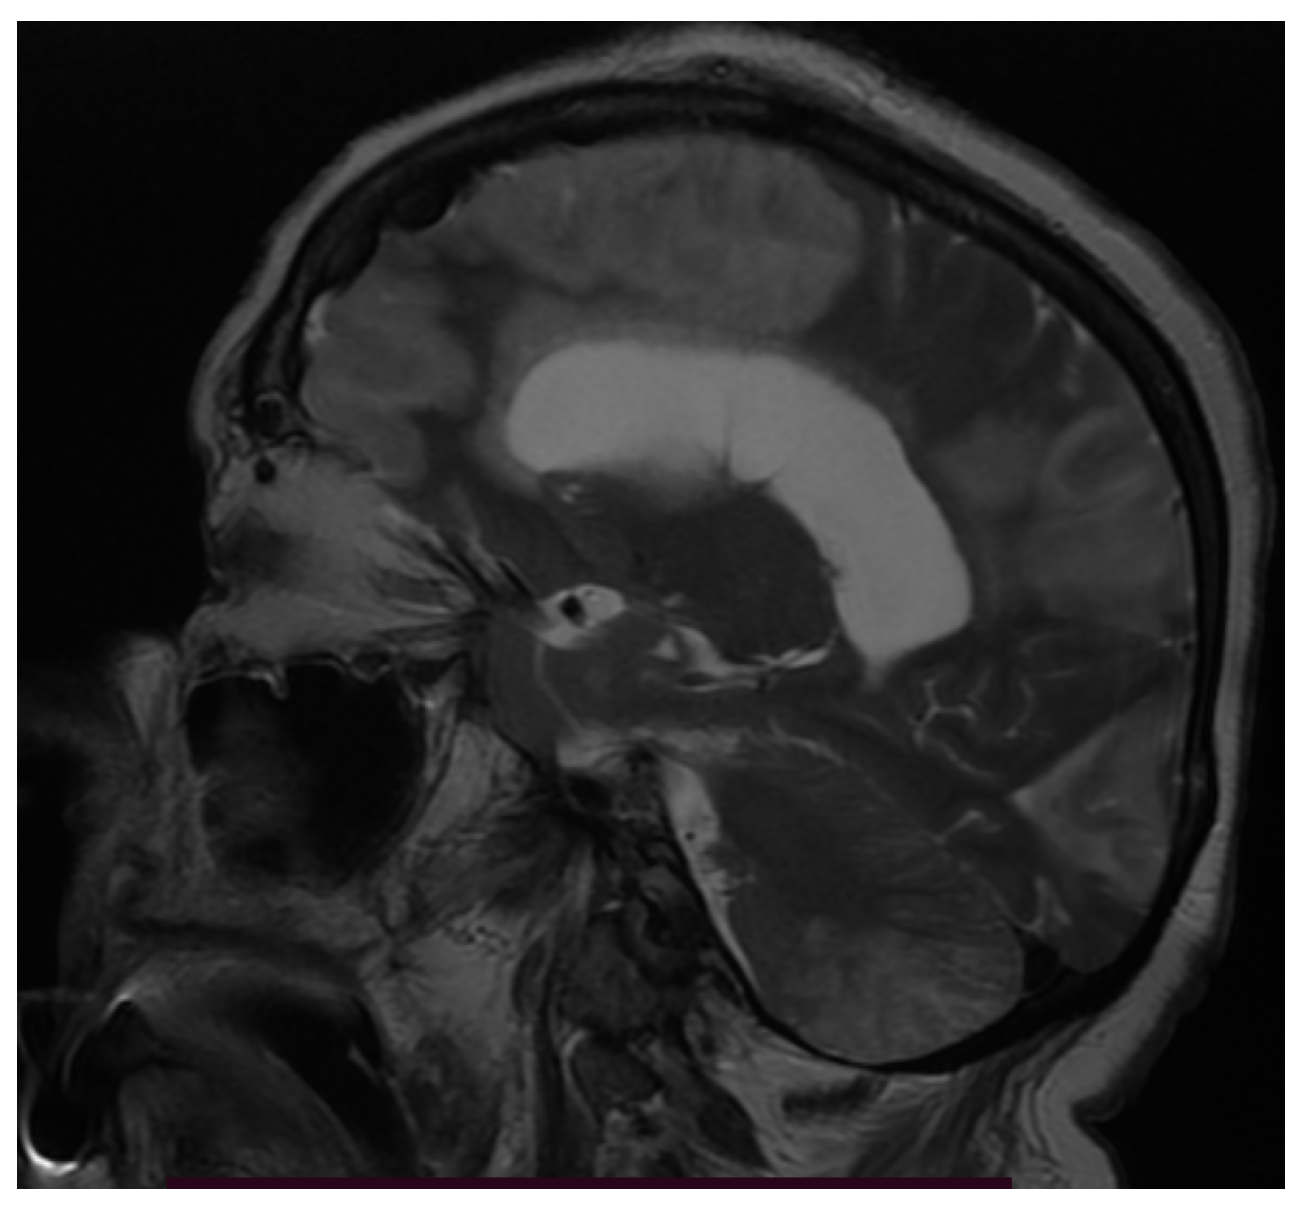

3.3. Neuroimaging